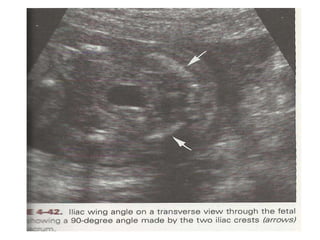

Lliac Wing angle

• Trisomy 21 fetuses have pelvic dysplasia and wider

lateral span of iliac wing as compared to normal thus

causing a widened iliac angle.

• Its measured in transverse view of fetal pelvis, the

iliac angle made by two iliac crests at pivot point of

sacral spine is measured.

•Mean iliac angle in downs is 80± 19.7 ºas compare to

63.1±0.3ºin normal, thus by taking 90º as cut off—

sensitivity is 36.8%.

Significance of Lliac Wing angle

• It is non reproducible due to variation in measurement

of angle.

Depending on 1) actual transverse level

2) intra and interobserver variation.

3) Orientation of spine, axial level

and GA.

• Not a useful marker of trisomy 21.